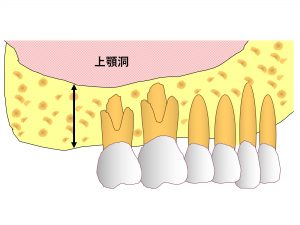

上顎の奥歯の上の方には、上顎洞という空洞があるのです。

まずはこの上顎洞について解説していきます。

上顎の奥歯は、顎の骨の中に埋まっていますが、

この骨はどこまでも骨ではありません。

頭が全て骨で埋まっていてはかなり重いです。

頭の骨には空洞があるのです。

その一つが上顎洞です。

上顎洞は奥歯の根の先にある空洞です。

上顎の奥歯を抜歯すると

歯は無くなりますが、骨は当然残ります。

このように骨が十分残るとインプラント治療はさほど問題なくできます。